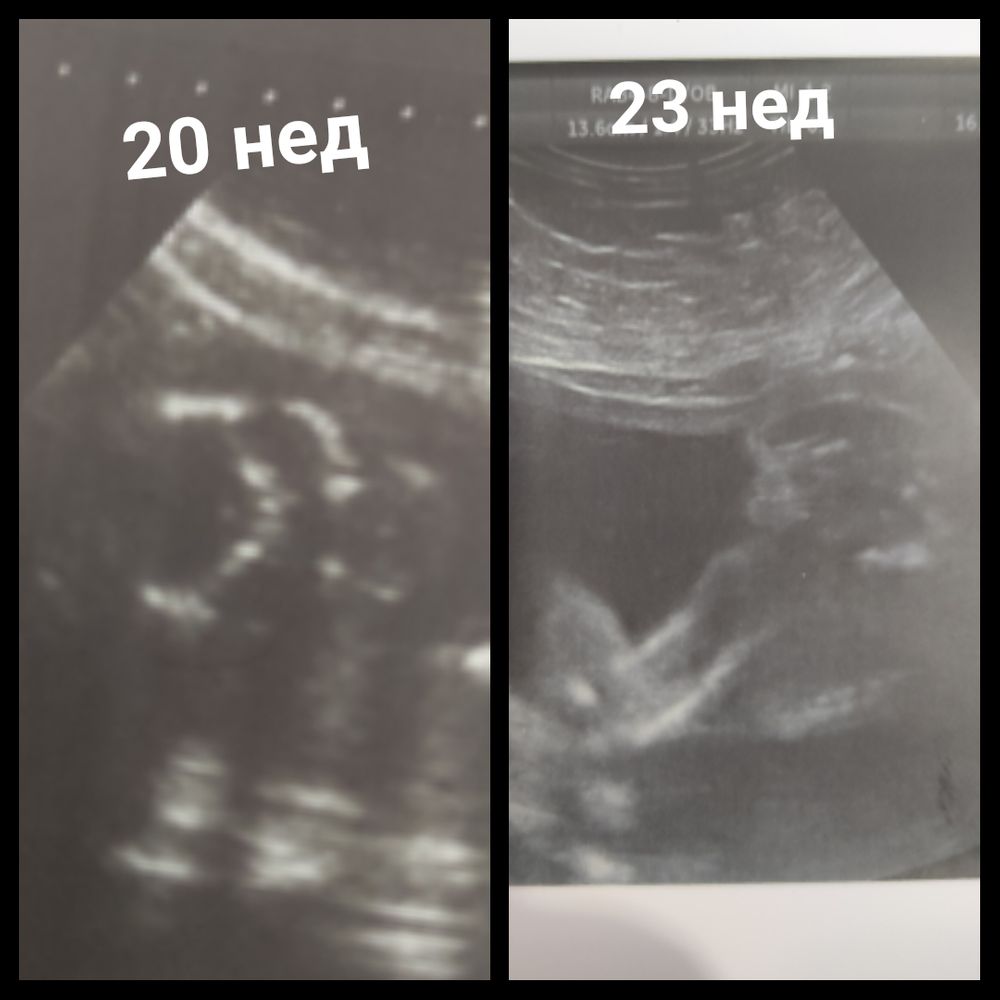

Мальчик или девочка?

Да, вроде, девочка на правом фото.

Ну если говорили вроде как девочка на предыдущем УЗИ, то я б всё-таки не выдержала и пошла ещё разок сейчас)А если точно сказали, то скорее всего так оно и есть

Лисичка, оба раза очень уверенно сказали, но мне так сложно поверить, ждала 30 недель и тут облом.

Dilyara, ну так не облом совсем. Просто не увидели, так как на таком сроке сложновато увидеть, ребенок уже большой. Девочка там у вас, точно.

Чашка утреннего кофе, дело в том, что у меня со старшим так было, на всех УЗИ был девочкой, родила мальчика, поэтому и паникую.. Но со старшим ни разу не дали фото "между ног", а тут два раза дали..

Dilyara, я по этим снимкам не очень понимаю, честно говоря, какого пола малыш. Вроде и не торчит ничего, но вроде что-то похожее на мошонку (но может это и не она, конечно) виднеется 🤔